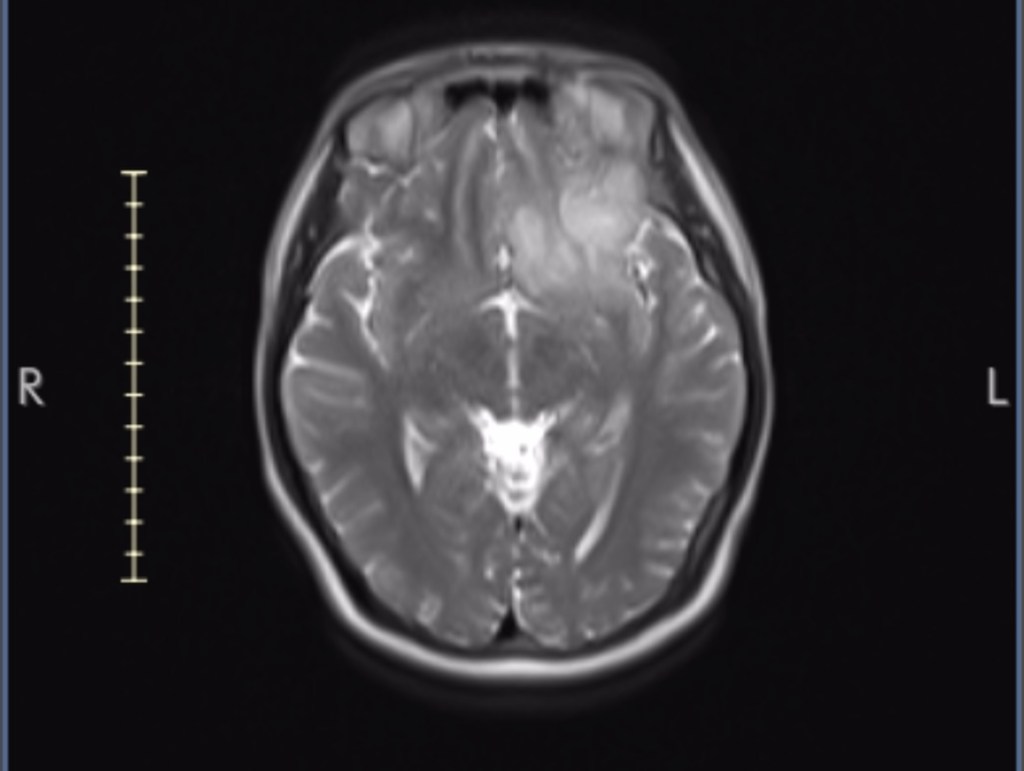

Then about a week or so later I heard from the NHNN. A week after that I had my second MRI, with contrast. This is where they inject some kind of dye/liquid into your body. It allows for the tumour to be seen better in the scan.

He confirmed there was something in my brain and that it could be a tumour. But that it could not be confirmed without going in my head to find out.